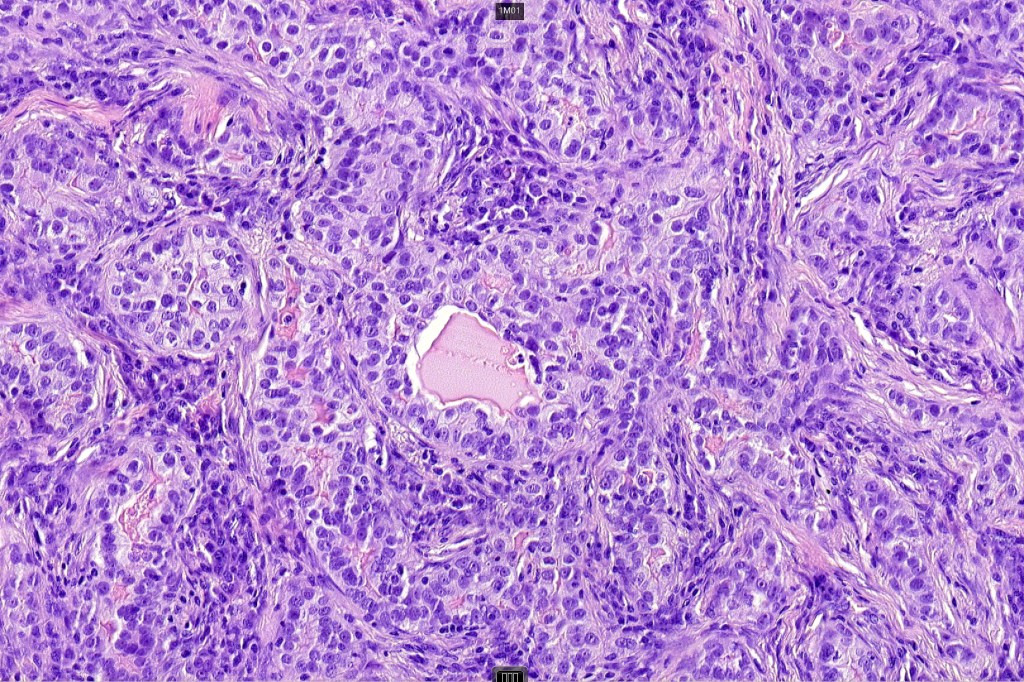

For comparison an actholytic squamous cell carcinoma- in cases of doubt, IHC and special stains for mucin will resolve the problem.

•Biphasic tumor combining squamous cell carcinoma and adenocarcinoma; the latter showing ductal and glandular differentiation

•Variable pleomorphism & mitotic activity but can be marked